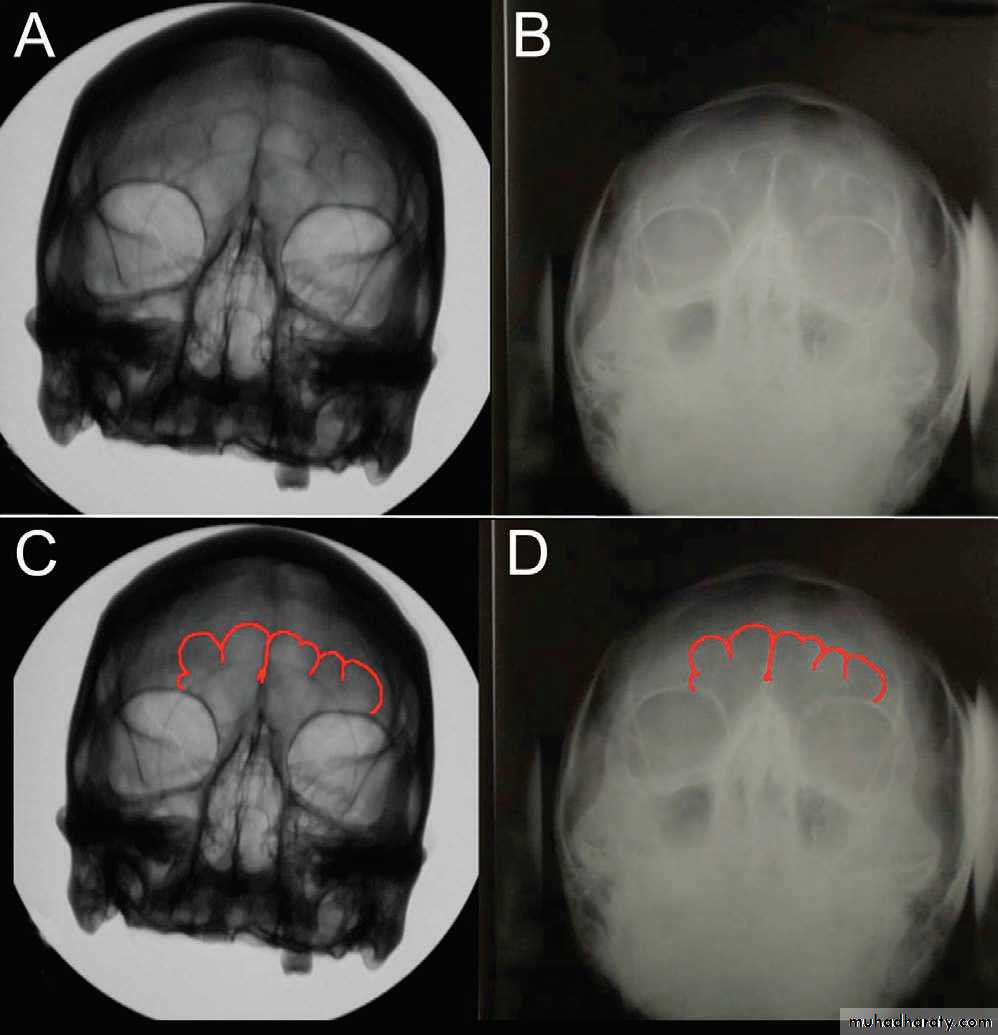

3) تحديد جنس صاحب العظام. من الصعب تحديد جنس صاحب العظام قبل بلوغ السن الفسلجي. ويصورة عامة تكون عظام الذكر اكبر حجمها واخشن ملمسها من عظام الانثى. وهنالك قسم من العظام يحمل خصائص جنسية مميزة ونخص منها بالذكر عظمي الجمجمة والحوض.

17• الجمجمة: تتميز جمجمة الذكر البالغ عن جمجمة الانثى بثقلها وخشونة ملمسها وكبر حجمها. وبكون النتوء الخشاوي والحرف القذالي بارزين وخشنين وكذلك الامر بالنسبة للجسر فوق الحجاج. تكون الزاوية الجبهية الانفية متميزة في جمجمة الذكر بينما تكون ضحلة في جمجمة الانثى. الوجيه اللقمي لقاعدة الجمجمة عريضا وقصيرا في جمجمة الانثى بينما يكون ضيقا اسطوانيا في جمجمة الذكر.. يتميز الفك السفلي عند الذكر بضخامته جسمه وارتفاع ارتفاقه الذقني وعرض ساقه الصاعد وحدة الزاويو بين الجسم والساق هع ضخامة اللقمة الفكية. بينما في الانثى يكون الفك السفلي صغيرا ناعم الملمس قليل الارتفاع عند ارتفاقه والقسم الصاعد ضئيلا واللقمة الفكية صغيرة.

قيافة العرق والسلالة من العظام: العروق البشرية الرئيسية هي: الابيض(القوقازي) والاصفر (المنغولي) والاسود (الزنجي). يستطيع الطبيب ان يحدد العرق من خلال فحص عظام الجمجمة والفك السفلي والاسنان. يميل محجر عين الزنجي الى الشكل المربع وعند المنغولي الى الشكل الدائري وعند القوقازي الى الشكل المثلث. تكون فتحات الانف ضيقة طويلة عند القوقازي وتعرض في قسمها السفلي عند المنغولي وتعرض في قاعدتها عند الزنجي. يكون القوسان الوجنيان ضخمان عند المنغولي.